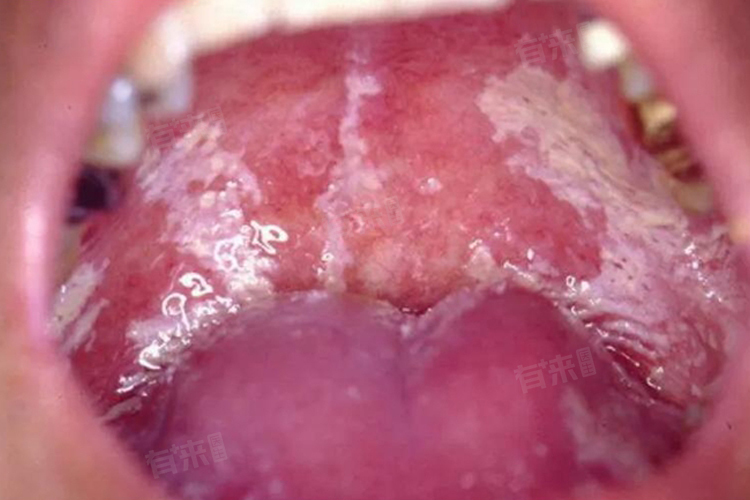

2、口腔感染:口腔念珠菌感染常见于婴幼儿、老年人及免疫力低下人群。患者口腔黏膜表面会出现白色凝乳状斑块,可附着于舌、颊、腭等部位,不易擦去,强行剥离后可见潮红糜烂面,可能伴有疼痛,影响进食,严重时还会导致吞咽困难。